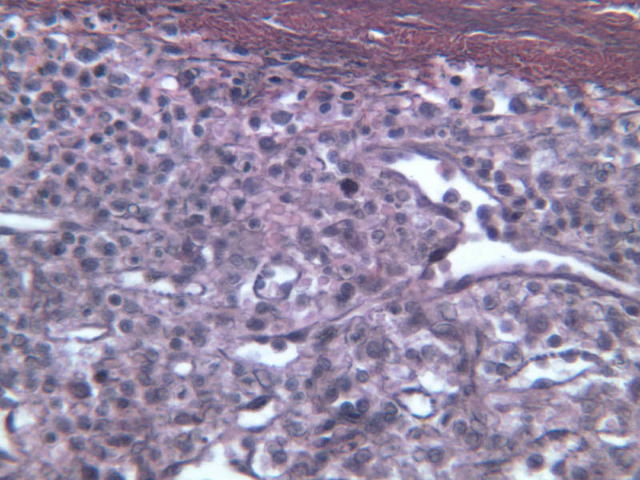

When foreign substances or antigens get into body tissues, such materials are usually taken into the lymph and transported to aggregations of lymphoid tissue called lymph nodes (slide A-32, H&E [2.5x-labeled, 10x, 20x, 40x] [2.5x-labeled, 10x, 20x] [2.5x, 10x, 20x-labeled, 40x]; A-33, H&E [2.5x, 10x, 20x, 40x]; A-34, retic [2.5x, 10x, 20x, 40x-labeled]; A-35, H&E [2.5x, 10x, 20x, 40x]), which are composed of lymph nodules invested by a distinct connective tissue capsule. The node is visibly separable into a cortex, where the densely stained nodules are concentrated, and a light staining medulla (A-32 [2.5x, 10x-labeled, 20x, 40x]). Strands, or trabeculae, of connective tissue separate the node into cortical compartments and join centrally in the node to emerge at the indented side known as the hilus. Small arteries and veins enter and leave the node at the hilus, being distributed in the node through the trabeculae. Capillary branches from the arteries are spread throughout the lymphoid node. Multiple afferent lymphatic vessels penetrate the capsule of the node, emptying into a subcapsular sinus which is a relatively cell-free zone (A-32 [2.5x, 10x, 20x, 40x-labeled]). Unidirectional flow of lymph from the afferent lymphatics into the sinus is assured by the valves in the vessels. From the subcapsular sinuses, lymph percolates through the relatively unobstructed cortical sinuses to the medulla. During this flow the lymph is filtered by phagocytes and foreign antigens are presented to lymphocytes by dendritic cells, the resident antigenpresenting cells. Nodules are formed as needed and subsequently disappear. Lymph finally reaches the medullary sinuses bounded by wide cords of tissue and passes out of the node at the hilus through the sole efferent lymphatic vessel.

The lymphoid tissue of a node is thus divisible into the nodules in the cortex and looser cords in the medulla. In the cortex, carefully examine a secondary nodule, composed of a dense outer rim of cells and a more loosely organized core (germinal center). In between the nodules find larger cells with pale, oval nuclei. These are reticular cells and will be most easily identified in the reticular-stained preparation (A-34 [2.5x, 10x, 20x, 40x] [10x, 20x, 40x]). The reticular fibers cells make up the CT scaffolding of the lymph node. Note that there are fewer reticular fibers in the germinal centers. Medium-sized cells with pale nuclei, particularly cells with a prominent nucleolus, may be progenitor cells of new lymphocytes. Macrophages present in the nodule are hard to distinguish unless they contain phagocytosed material. In the medulla, cell types in the cords are easier to distinguish because cytoplasmic size and extent can be seen. For example, the differences between large lymphocytes and reticular cells can be seen. Several types of granular leukocytes are frequently found in the cords in addition to the expected population of lymphocytes and plasma cells.

Another important structure to identify is the high-endothelial or post-capillary venule (A-32, [2.5x, 10x, 20x, 40x-labeled] [10x, 20x, 40x] [2.5x, 10x, 20x, 40x-labeled]; A-33 [2.5x, 10x, 20x, 40x-labeled]). Lymphocytes from the blood enter and leave the lymph nodes through post-capillary venules. These structures are characterized by high columnar or cuboidal endothelial cells. They are most often located in the paracortical zone, which is at the junction of the cortex and medulla. Locate a postcapillary venule on slide A-32. What advantage is gained by having lymphocytes entering and leaving the lymph node?